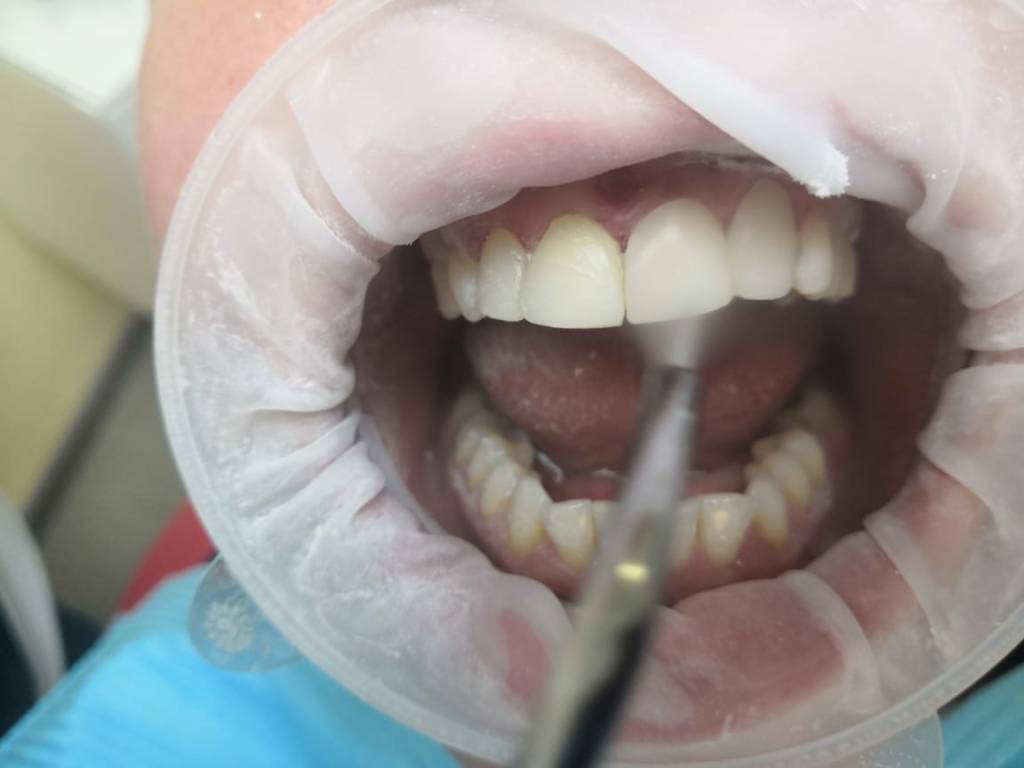

Клинический случай : Пациентка обратилась с жалобами на пломбы передних резцов (верхняя челюсть), была предложена реставрация